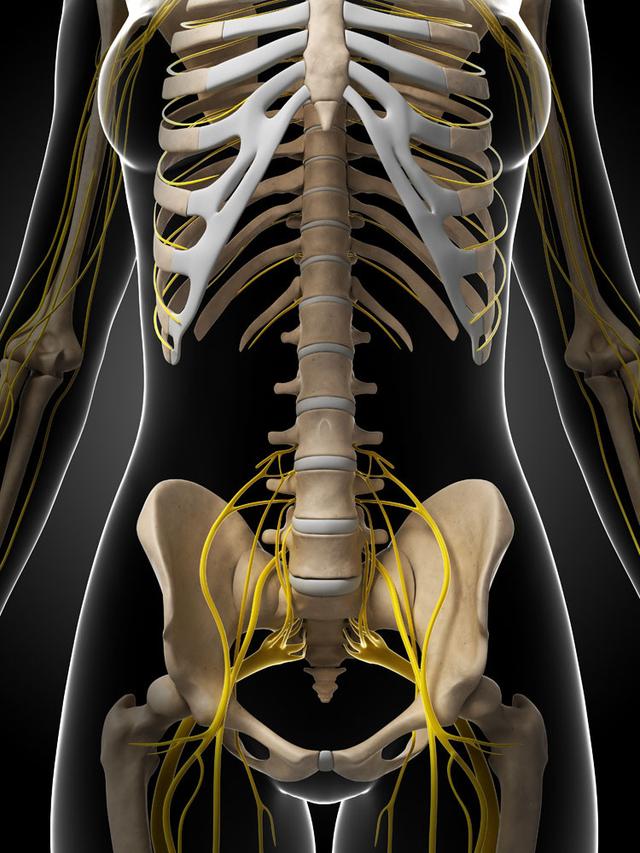

从一方面来说,人类是弱小的,容易生病,容易受伤,但从另一方面来说,人类也是强大的...